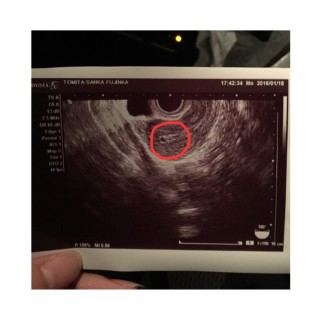

ちょっと見えにくいですが真ん中下の方だそうです。 海外にいたのですが、環境や生活を変えてみると(不妊治療に)いいと言われて古里に帰ってきての治療でした。 治療をしている病院はかかりつけの病院からの推薦で、人気のある所ですが二ヶ月待ちで始めることができました。 サプリメントなどを飲む事から始めて約3か月で妊娠(一応)でき、帰ってきてみてよかったです。 この先どうなるかまだまだ分かりません。低体温なので腹巻きしてあったかくしています。

3回目の内診でやっと胎嚢を確認することが出来ました( ; ; ) 今は4週目みたいです! この2週間は本当に毎日不安で不安でソワソワしちゃって 家事もろくに手につかなかったです(>_<) 昨日確認出来てほんっとに嬉しいです♡ 次は2週間後に心拍を確認します! 赤ちゃんの生命力を信じて待ちます!

生理が遅れて6日目で陽性(^^)次の日に病院にいったら『妊娠してますね♪まだまだ小さいのでまた1週間後にきてください♪』半信半疑だったのでエコーみたときは幸せでした。不安ですが大好きな人との赤ちゃんを何があっても守ろうと思いました(*^^*)

正常妊娠です。

と、言われた瞬間から、顔がにやけっぱなしで、

母も喜んでくれました。二週間後、心拍確認♪待ち遠しい( ´艸`)

3つのたいのうがありました(*^▽^*)

三つ子ちゃんかな?

つぎの検診では、3つともに心拍がみえますように!